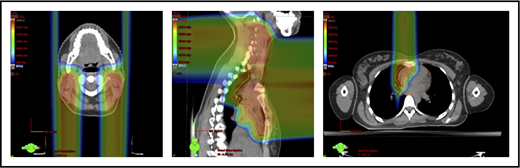

With regard to field arrangements, the PBSPT technique for an anterior upper mediastinal and lower neck target usually requires 1 (repainted) or 2 anterior fields. For more complex target volumes, targets can be divided into 2 or more parts (eg, neck CTV, mediastinal CTV, and axillary CTV), and a multifield plan can be used (Figure 5). For cases that involve lower (posterior) and upper (anterior) mediastinal targets, a combination of posterior and anterior fields can maximally spare the heart and lungs (Figure 6). For upper neck targets, lateral or posterior fields can avoid the oral cavity/salivary structures. For axillary targets, a posterior field can help to spare breast tissue. Although these various field arrangements can be used in PSPT, gradient matching is simpler in PBSPT when the fields overlap or oppose, obviating the need for feathering.

Scans for a young woman in whom the target included mediastinal, left parasternal, and left axillary regions. One anterior field was used for the mediastinum, and a separate posterior field was used for the axillary region.